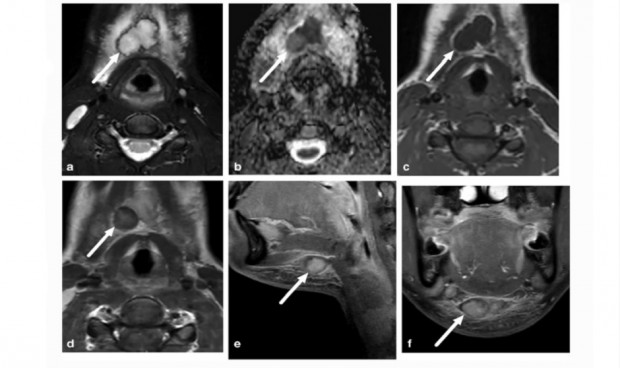

"La resonancia magnética (RM) es un método de imagen factible y preciso para diagnosticar las infecciones pediátricas del cuello". Así lo explican un grupo de investigadores que, según los datos del estudio, "la precisión diagnóstica de esta técnica es superior a la proporcionada por la tomografía computarizada (TC)", explica Janne Nurminen, el autor principal del estudio.

En cuanto a los beneficios adicionales de la RM, sobre todo en niños, "se incluyen la falta de radiación ionizante", según Nurminen quien asegura que "en los grupos de edad más jóvenes se enfatizan las infecciones del espacio retrofaríngeo y la linfadenitis supurativa, lo que refleja las diferencias anatómicas entre niños y adultos". Unas diferencias que "requieren especial atención y habilidades de interpretación radiológica", señala Nurminen en el estudio publicado en la plataforma Springer.

En este sentido, Nurminen detalla que "la distribución anatómica de la ubicación de la infección fue significativamente diferente entre los niños en comparación con los adultos". Igualmente, añade que "las pruebas realizadas indicaron que las infecciones del espacio retrofaríngeo eran más comunes entre los niños (en un 24 por ciento) que entre los adultos (en un 3 por ciento), al igual que los ganglios linfáticos infectados (24 por ciento frente al 7,3 por ciento)".

Sin embargo, "las infecciones periamigdalinas/parafaríngeas fueron más frecuentes en adultos (44 por ciento) que en niños (22 por ciento)", añade Nurminen. Además, el experto señala que "las infecciones de origen dental también fueron más frecuentes en adultos (31 por ciento) que en niños (11 por ciento)". Hubo diferencias adicionales y más sutiles en la distribución de la ubicación de la infección en el grupo de estudio pediátrico (de 0 a 17 años), especialmente en lo que respecta a las infecciones del espacio retrofaríngeo y la linfadenitis.

"De los 20 pacientes de 7 años o menos, solo uno tenía una localización principal diferente al espacio retrofaríngeo o linfadenitis", detalla Nurminen. Además, no se observaron infecciones del espacio retrofaríngeo entre los pacientes de 8 a 17 años, y solo dos tenían linfadenitis en este grupo de edad. Este patrón de resultados sugiere que las infecciones retrofaríngeas y la linfadenitis tienden a ocurrir en niños más pequeños.